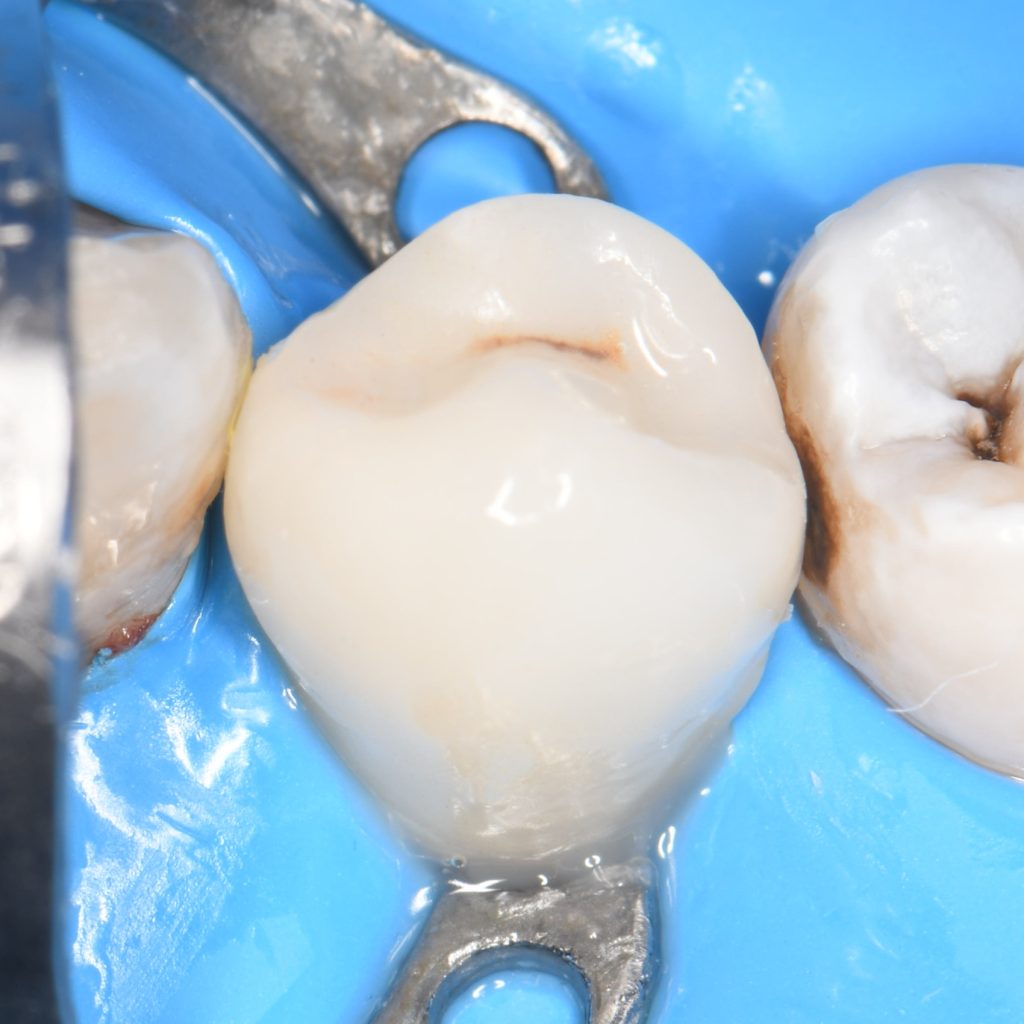

And replacing the dentine with ribbond and Ever X composite in order to strengthen the remaining tooth against fracture, Both fiber types improve fracture resistance and the fracture mode of structurally compromised teeth is equally efficient. Application technique deserves attention. Ribbond could be placed in a single layer at the cavity floor, whereas EverX Posterior should replace missing dentin in an anatomically shaped way.

We complete the Biobase by placing conventional composite on the fibers and preparing the tooth for indirect restoration

Ribbon application

Ever X posterior application